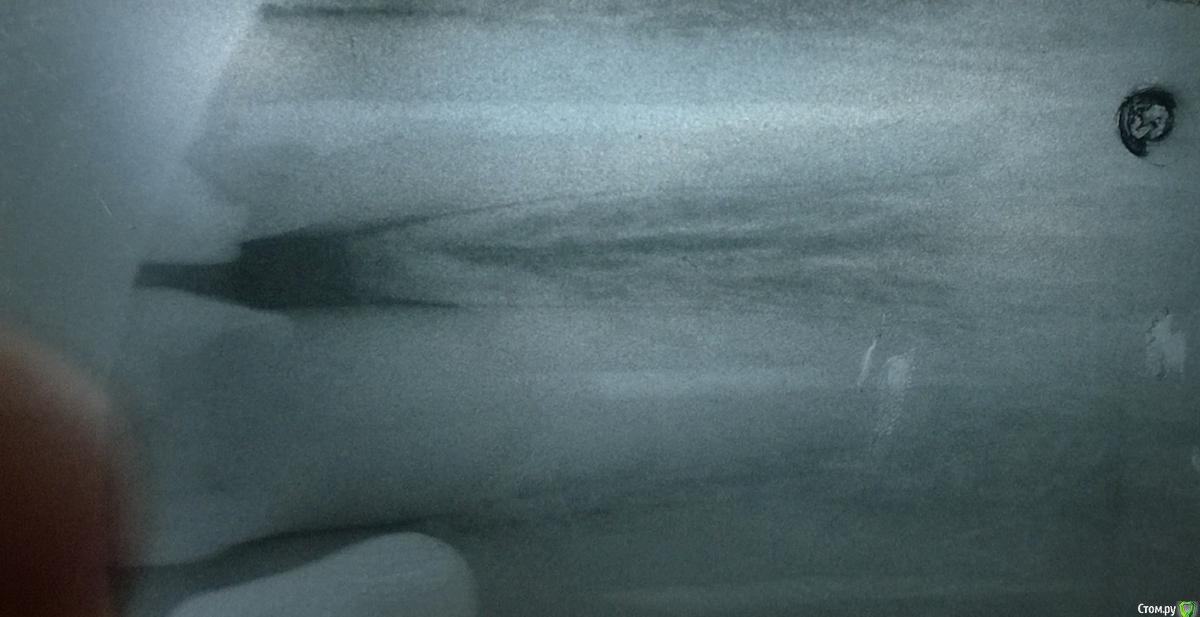

Arcus Опубликовано 6 декабря, 2014 Поделиться Опубликовано 6 декабря, 2014 В этом году закончил интернатуру, поэтому любая критика будет очень полезна Пациентка 58 лет пришла с обострением периодонтита зуба 11, перкуссия резко болезнена, был отек переходной складки, но инфильтрата я не пропальпировал (разрез по переходной складке сделал, но гнойного экссудата не получил , дренаж не ставил).Вот протокол по которому работал:1. Обезболивание2. Наложение коффердама3. Создание доступа (пригодилась эта статья, спасибо Kivilgar)4. Введение RC-prep и прохождение k-file 10 с апекслокатором до 0.0. Измерил линейкой и от этой длины отнял 3 мм, и начал обрабатывать канал на эту длину помощью Protaper S1, S2. Промыл гипохлоритом, подключил апекслокатор и прошел последние 3 мм К файлами 10,15,20,25 сделал рентгеновский снимок. По нему файл был на уровне рентгенологической верхушки, пришлось уменьшить рабочую длину еще на 0,5 мм.5. На полную рабочую длину обработал корневой канал Protaper S1, S2, F1, F2, потом у апекса дорабатывал K файлами NiTi 30,35,40. После каждого файла промывал канал гипохлоритом натрия и проводил рекапитуляцию 10 файлом.6. Медикаментозная обработка перед временным пломбированием. Гипохлорит натрия, высушил пинами, хлоргексидин 2% на 2 мин, высушил пинами, спирт 95%, высушил пинами. Ввел Metapaste, притрамбовал бумажным пином, ватка, временная повязка Кависил. (верхний зуб) Назначил найз по 1 таб 2 р в день, 5 дней и линкомицин 2 кап 3 раза в день 5 дней. (тут прошу совета, нужно ли назначать антибиотик при обострении периодонтита, когда имеется отек переходной складки. При периоститах всегда назначаю антибиотик и НПВС, разрез до кости на всю ширину инфильтрата, промывание и дренирование. Но в данном случае я не смог получить гноя)7. Через 3 дня на осмотре слизистая слиплась из-за того, что не было дренажа, пальпация слабоболезнена, перкуссия слабоболезнена. 8. Через 1,5 недели пациентка жалоб не предьявляет, перкуссия безболезненная, пальпация по переходной складке безболезненная, однако, в проекции верхушки корня я обнаружил плотное, округлое образование слабоболезненное при пальпации. Свища на слизистой нет. Что это может быть? На рентгене особого разрежения костной ткани нет.9. Наложение коффердама, снятие временной пломбы, вымывание кальция гипохлоритом натрия. Фото с мастер-штифтом 40, 0.4. Вот по фотографии явно видно, что штифт немного вышел, хотел же укоротить его на 0,5 мм, ан нет, не сделал. (коффер соскочил во время снятия для рентгена, пришлось без него делать).10. Опять наложил коффер, медикаментозная подготовка перед пломбированием - ЭДТА (Эндожи 2) в канал на 2 мин, немного его активировал гуттаперчевым штифтом. Промыл дистиллированной водой, хлоргексидин 2% вначале мыл, а потом на 2 мин оставил в канале, высушил пинами, промывание гипохлоритом натрия 20 мл с активацией штифтом. Смотрю осадок бурый выходит из канала, ну блин Вот как этого избежать? Водой еще мыть? Причем в первое посещение такого не было. Высушил каналы, промыл 95% спиртом и оставил на 1 мин. Высушил пинами. Осадок очень вреден? Я его потом спиртом вымывал, вроде пины стали чистыми, но как там в дентинных трубочках я не знаю.11. А потом латеральная конденсация, на мастер-файле ввел AH+ в канал, потом добавлял штифты. Отжег в верхней трети, изолирующая из Vetrimer и Кависл.Отправил на рентген, а там такое Паф, да еще вроде штифт вылез, хотя точно не знаю. Оставить так или перепломбировывать? 12. Никогда больше не буду латералить с мастер-штифтом 0.4 конусности, хоть он хорошо клинил в канале, но места для дополнительных штифтов очень мало.Что изменить и дополнить в инструментальной и медикаментозной обработке? 1 Ссылка на комментарий